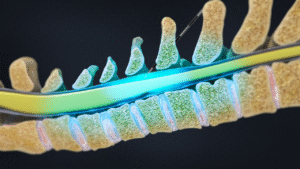

- Minimal-invasive Eingriffe

- Neuromodulation